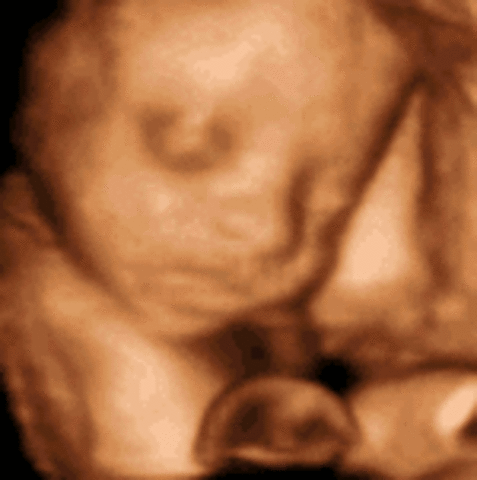

• Week 20

Week 20

This is the halfway mark through pregnancy. The baby can hear voices and be familiarized with them. Growth of hair on the rest of the body is starting.

• Week 22

Week 22

The eyebrows, eyelids, and fingernails are developed. The tongue's tasetbuds are forming.